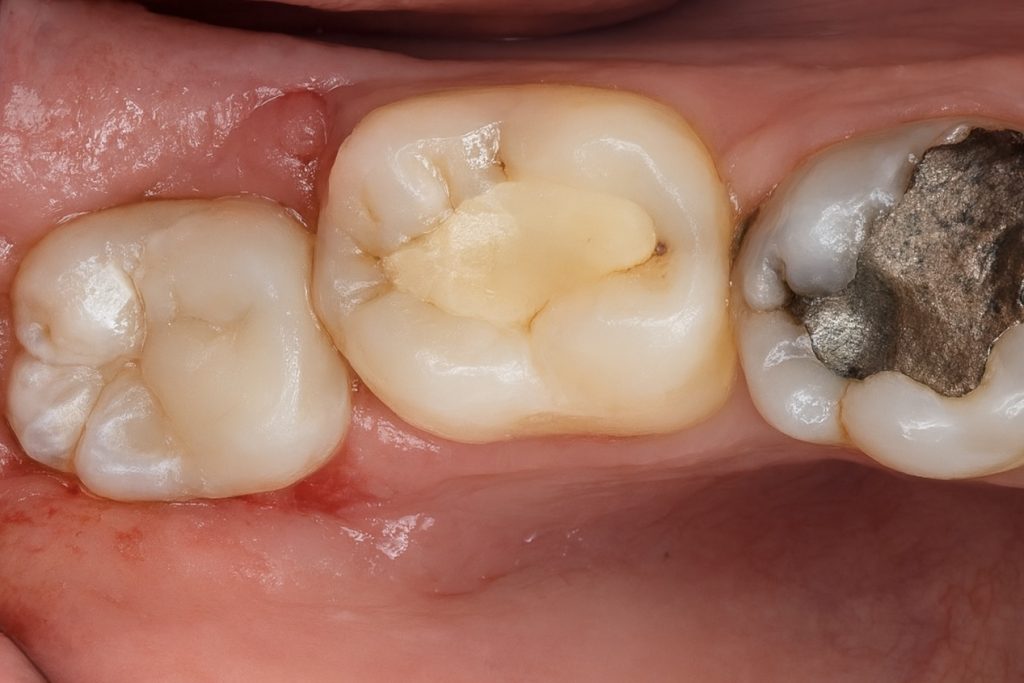

The patient presented with a distal carious lesion on a partially infra-occluded mandibular third molar exhibiting food impaction and sensitivity (Fig 1). CBCT and radiographs confirmed a deep Class II lesion extending sub-gingivally, but with adequate periodontal attachment for isolation and restoration.

- Fig 1: Pre-operative view showing distal caries on infra-occluded third molar.